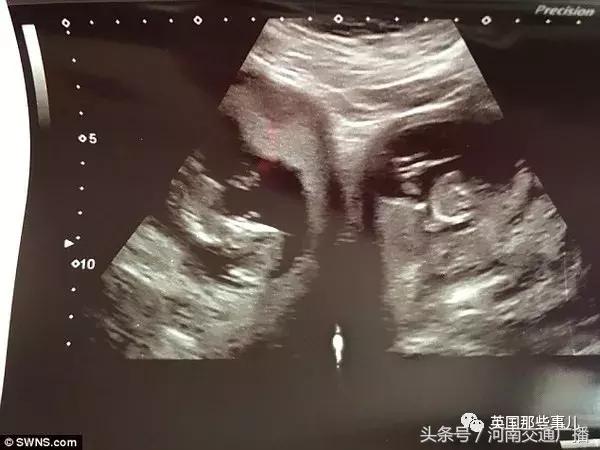

经过检查确认她怀了一对双胞胎,

到了今年2月份,在一次检查中,医生发现了异常情况,

詹妮弗拥有两个子宫,

之前所说的双胞胎胎儿,正分别孕育在她的两个子宫内!